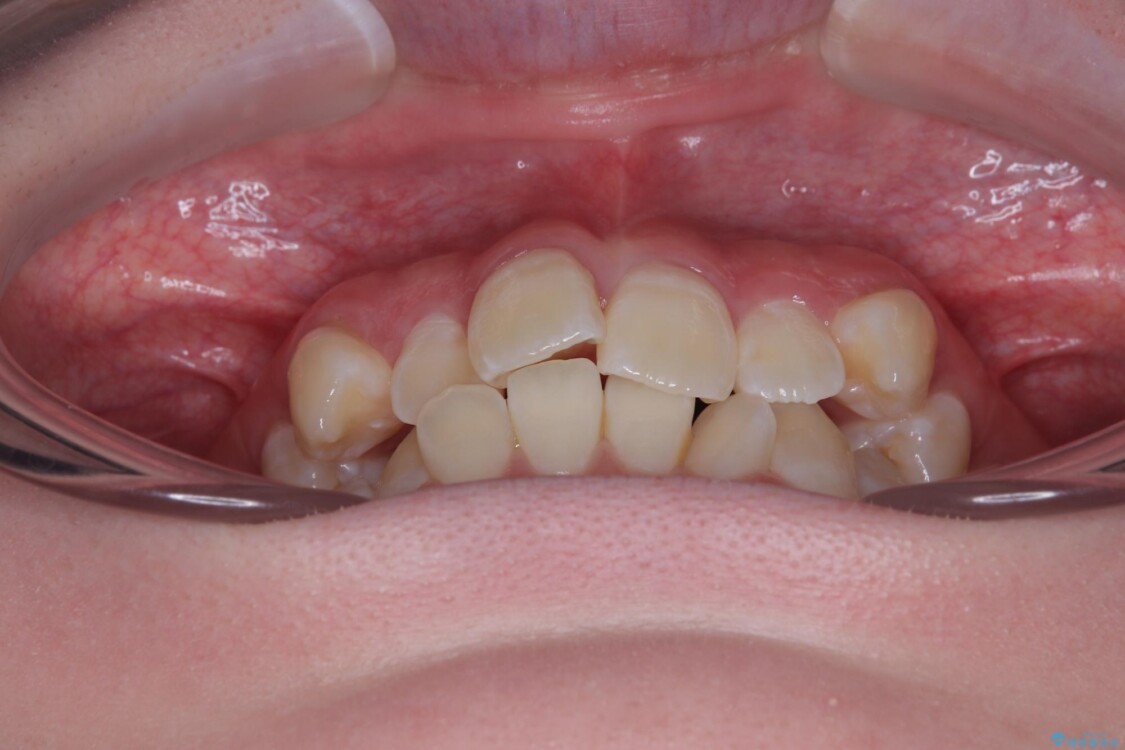

「前歯のデコボコ(叢生)をきれいに整えたい」とのことでご来院されました。

治療前

• 【モニター】前歯のデコボコをスッキリ解消!目立ちにくいワイヤー矯正でスピーディに治療完了 治療前画像